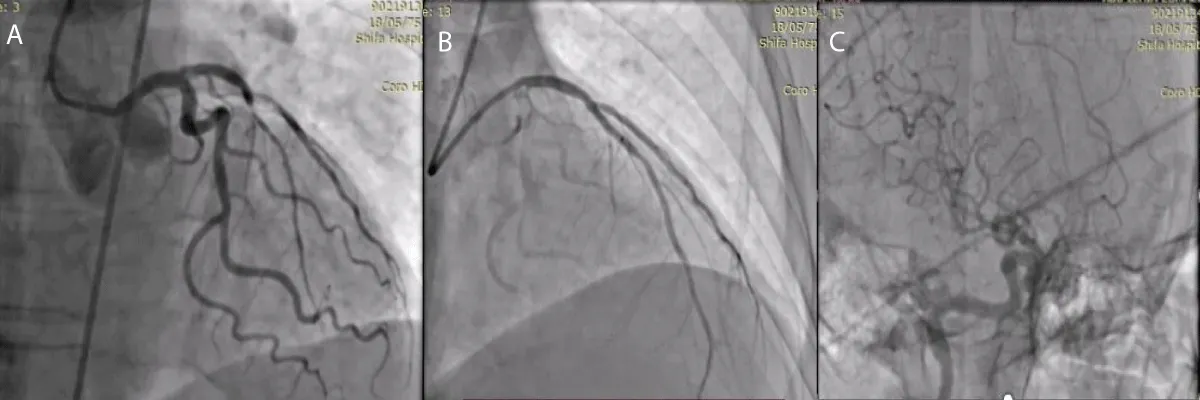

A 67-year-old male patient wasn’t known case of any chronic illness, and presented with chest tightness radiating to both shoulders associated with sweating and nausea for 2 hours, on examination: Patient was conscious, oriented, sweaty, not in respiratory distress and his blood pressure: was 150 / 90 mmHg, Temperature: 37 °C, Heart rate: 80 bpm O2 saturation: 99%, Electrocardiography (ECG) was done at the Emergency department which was showing ST-segment Elevation in V1 - V6 leads with reciprocal changes in inferior leads II, III, AVF. Aspirin 300 mg, clopidegrel 600 mg and morphine 3 mg were given then according to AL-Shifa Hospital protocol, patient was transferred to cardiac catheterization department for primary Percutaneous Coronary Intervention (PCI), then coronary angiography showed total occlusion of proximal left anterior descending artery (LAD), other vessels were normal, So coronary wire passed freely in LAD and resolute integrity stent 3 x 18 mm (drug eluting stent) was deployed successfully in proximal LAD, during that patient developed sudden onset of left upper limb and left lower limb weakness, National institute of health scale score (NIHS) score 8, So cerebral angiography was done and it was showing TICI Flow III with residual thrombus in MCA (Figure 1), by microcatheter in right middle cerebral artery, intra-arterial alteplase 8 mg was given, then weakness completely was resolved after 10 min with no residual neurological deficit, after that patient was transferred to coronary care unit for 2 days and discharged with good general condition and mRS (0), then he was maintained on aspirin 100 mg daily, clopidogrel 75 mg daily, atorvastatin 80 mg daily and bisoprolol 5 mg daily. Echocardiography: suggested apical hypokinesia with 1.2 x 1.1 mm thrombus, impaired left ventricular ejection fraction: 36%. Follow-up after 3 months was done and the patient had mRS 0.

Figure 1: A- coronary angiography, total occlusion of proximal LAD, B- after stent deployment in proximal LAD, C-cerebral angiography, TICI Flow III with residual thrombus in MCA.